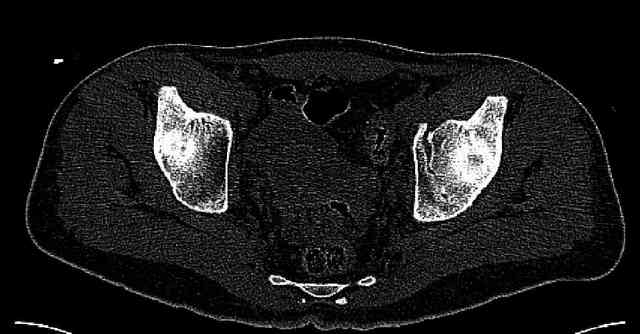

The joint is non-concentric as the head appears to be either "following the caudal segment", or the dome component is displaced from the tethered head... or so it seems... and he's young... so, many fracture surgeons would recommend reduction and fixation.

So we must decide preoperatively which part is the displaced segment?

It's difficult to know from these few selected images which component of the injury (was before and now) should be deemed the "soon to be mobile"

segment. It's my best guess that it is the caudal portion and there exists a healing fracture line somewhere thru the posterior column...one image

suggests it. If true, its early healing/union should be disrupted, and the resultant fragment mobility then allows accurate reduction.

Some more images. Does it help to guess which part of the acetabulum is displaced?

Normal appearing SI joints and a healed posterior column limb... my bet's on caudal segment displacement.